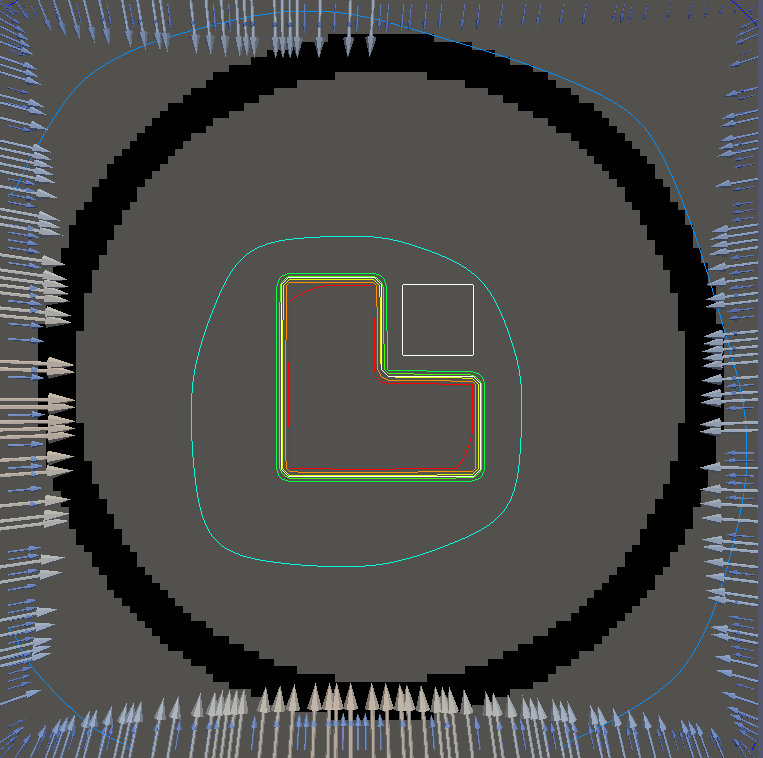

For testing, we use three tumor/risk region regions similar to those in [13]. Specifically, we define the regions in Table 3 and are shown in Figure 1; the void region is shown in black and the tumor and risk regions are traced in white. In the basic target case, seen in Figure 1(a), the tumor region is a box, as is the risk region. The second, intermediate target case, seen in Figure 1(b), involves an L-shaped tumor around a box-shaped risk region. Finally, the complex target case in Figure 1(c) involves a C-shaped tumor around a risk region.

We conclude with a final set of numerical examples which restrict the location of the source by altering the definition of Here we require that on one side of the boundary. For the basic and intermediate case, we require that the external source not come from the left side of For the complex case, we disallow sources on the right side (as the optimal source is nearly zero on the right side in the complex case for ). Figure 4 shows the optimal solution for both problems, using the same penalization parameters used in Figure 2. The optimal dose for is significantly worse, with the tumor in the intermediate and complex cases getting a dose below However, the tumor cells have a survival of or less for each case and the risk region has a survival rate of or higher in each case.